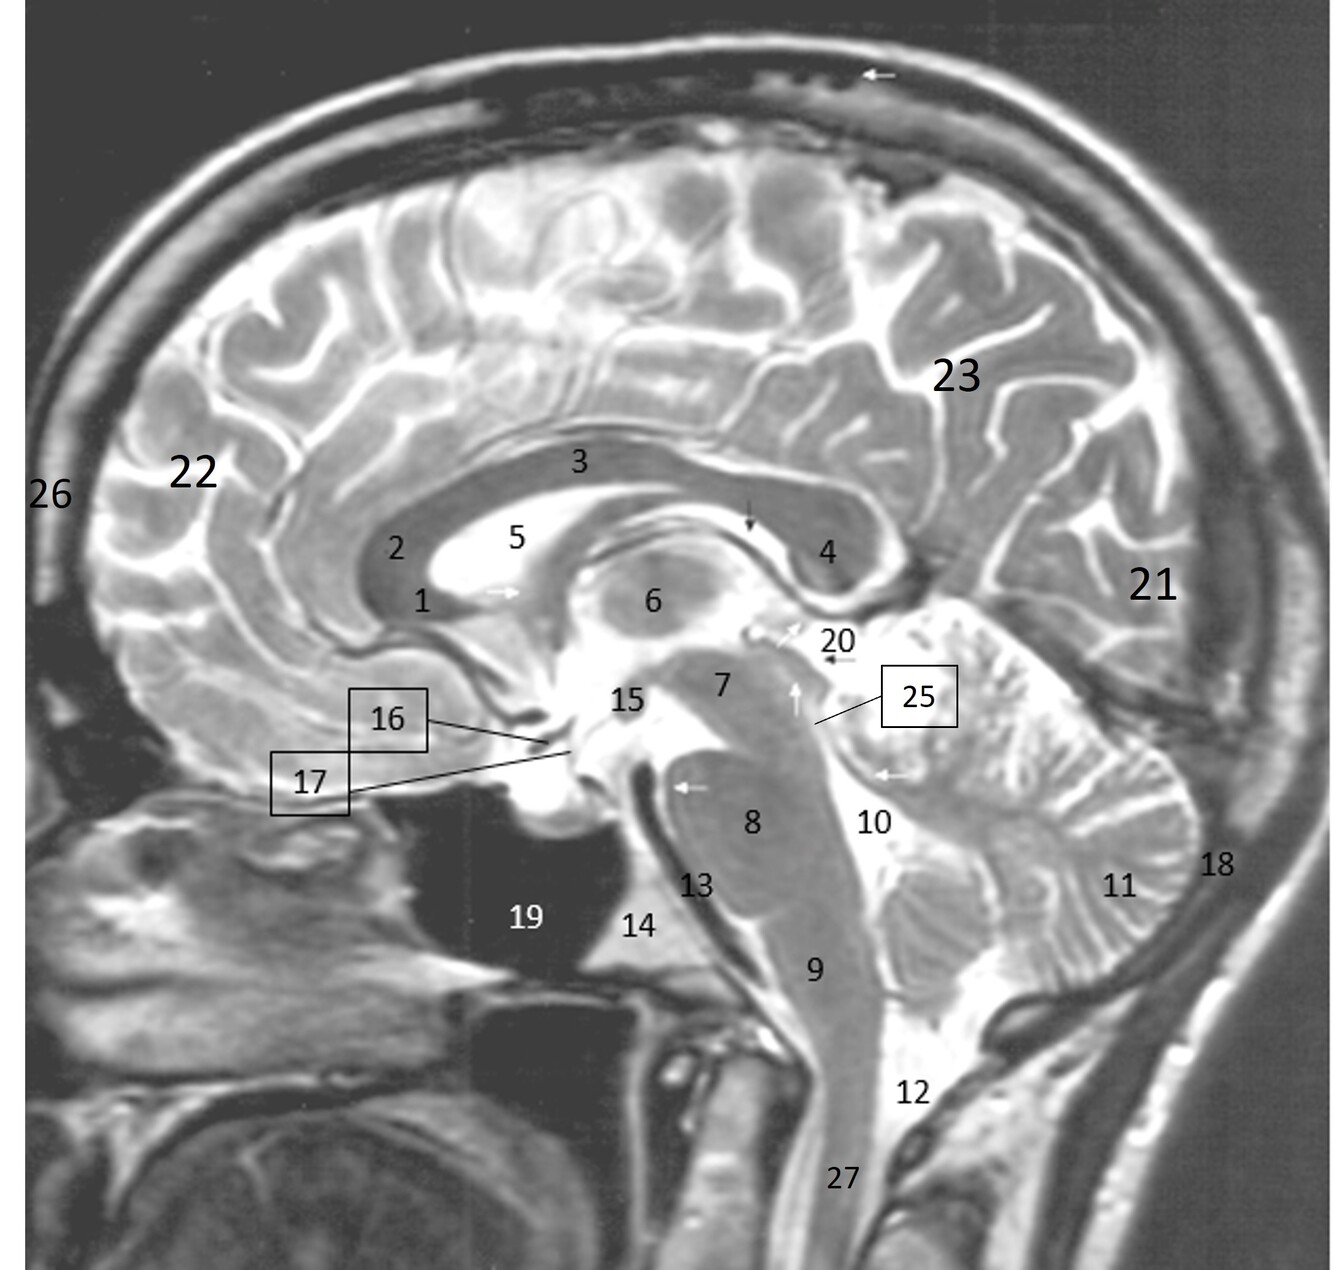

16

Label 19-27

A

19=Sphenoid sinus

20=Quadrigeminal cistern

21=Occipital lobe

22-Frontal lobe

23-Parietal lobe

25-Cerebral aqueduct

26-Frontal bone

27-Spinal canal

15

Label 10-18

10-4th ventricle

11=Cerebellum

12=Cisterna Magna

13=Basilar artery

14=Clivus

15-Mamillary body

16=Optic chiasm

17=Infundibulum

18=Occipital bone

14

Label 1-9

1=Rostrum (CC)

2-Genu (CC)

3-Body (CC)

4=Splenium (CC)

5=Lateral ventricle

6=Thalamus

7=Midbrain

8=Pons

9-Medulla oblongata